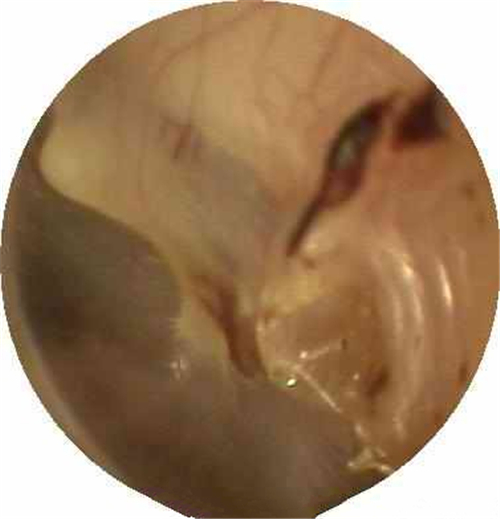

炎症導致鼓膜穿孔